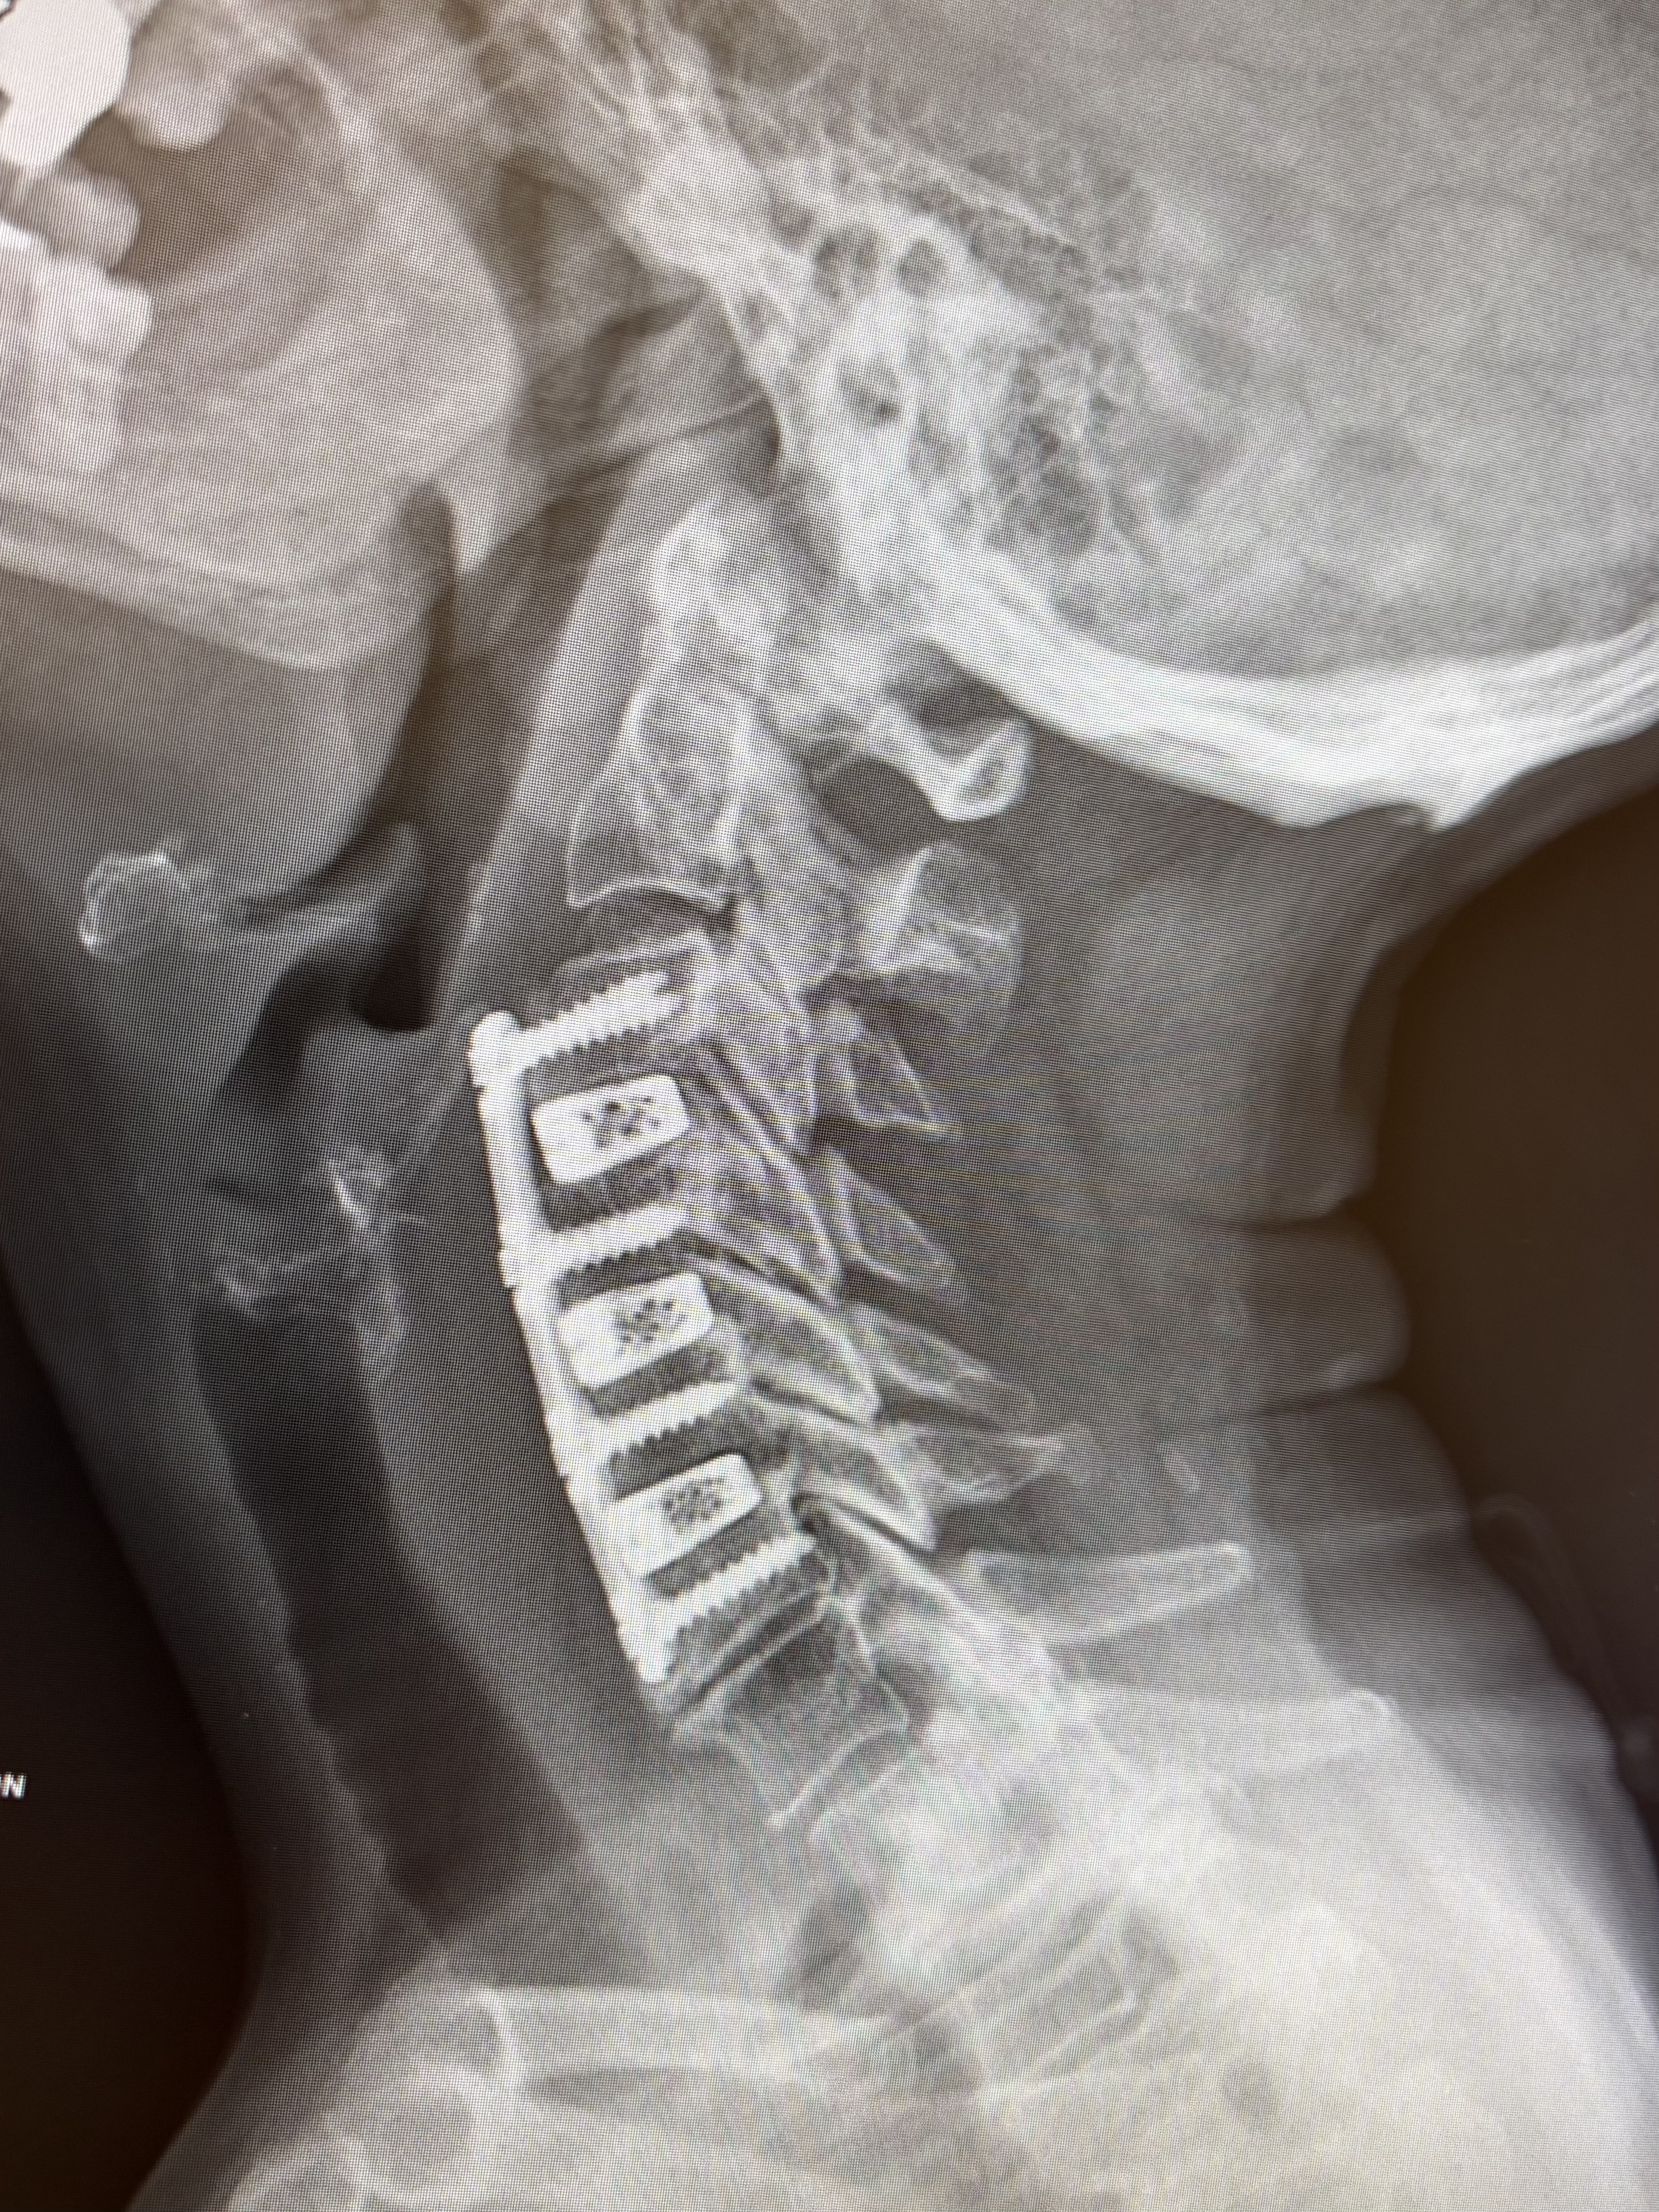

Dr. Rod Oskouian is an absolutely amazing neurosurgeon when you need a true expert to perform a difficult surgery. I was told by another spinal surgeon that I could become paralyzed in both arms and not be able to feed myself soon because of the severe narrowing of my cervical spinal canal and I would need to undergo a posterior approach 4 level cervical fusion surgery which is extremely painful and difficult on the patient. He also stated that only a two level fusion could be done by an expert spinal surgeon from an anterio... read more